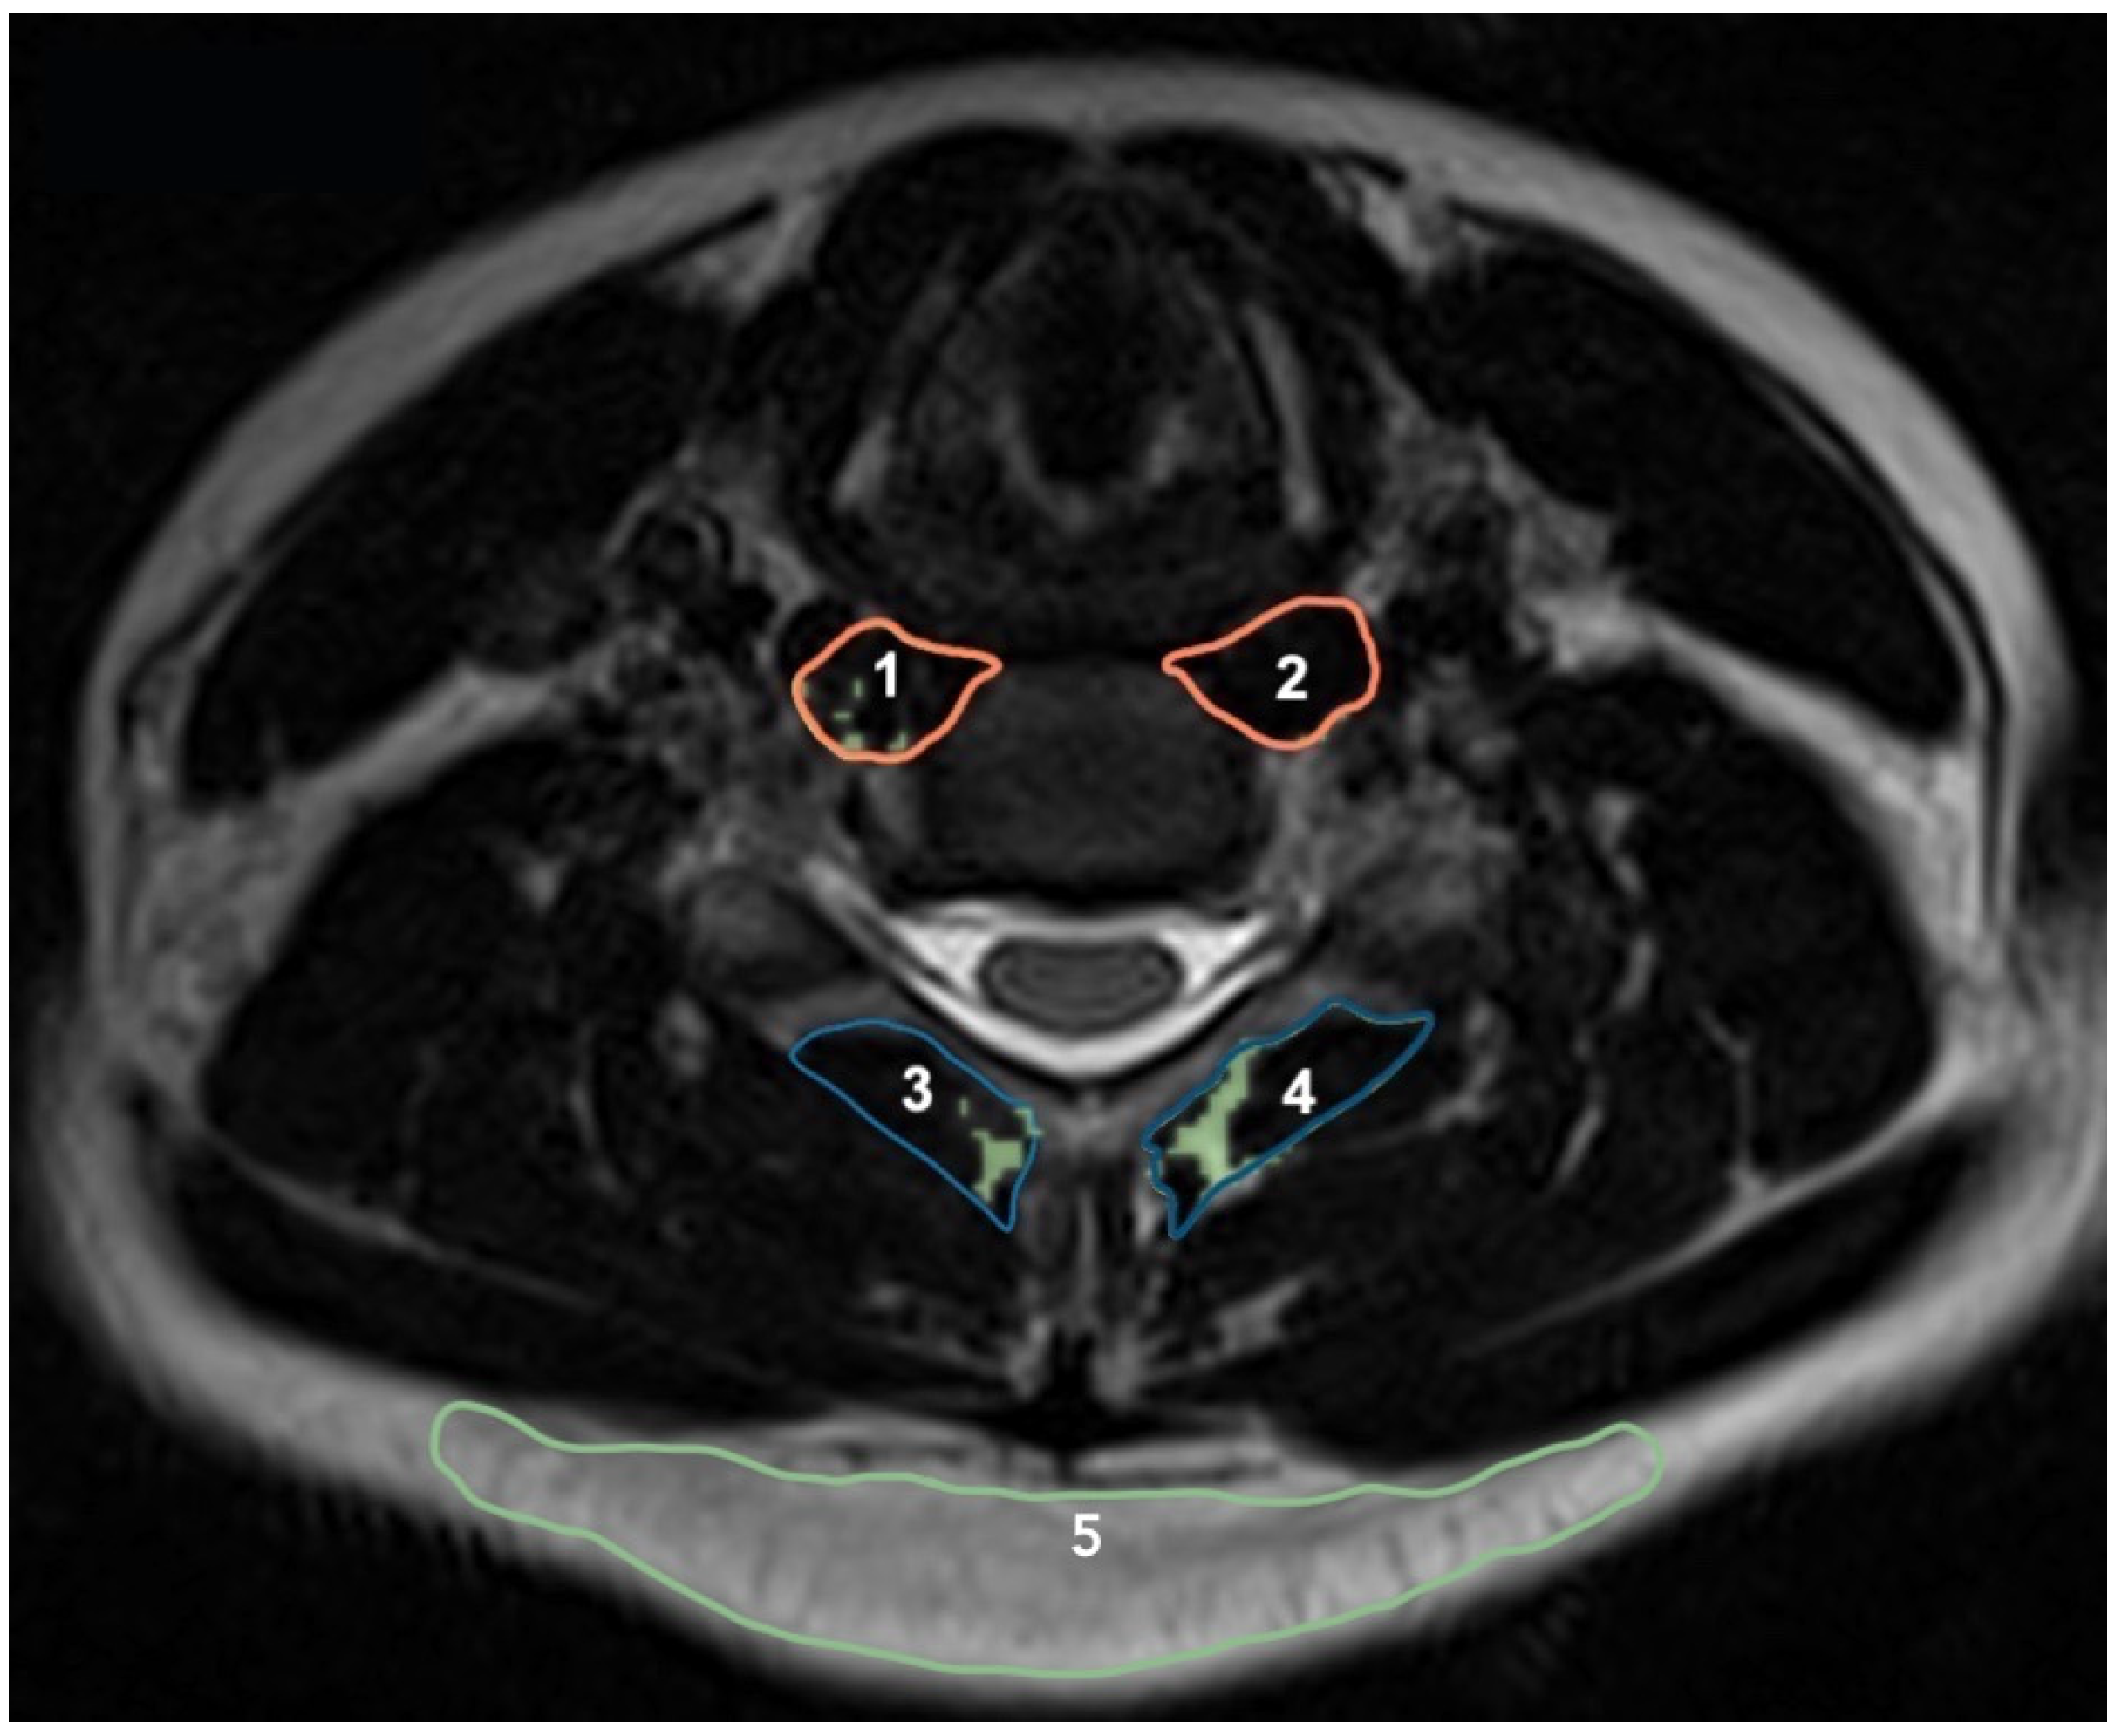

MRI acquisition of muscle morphological measures was obtained using a conventional spin-echo pulse sequence, time repetition of 1250 ms, time echo of 123 ms, resolution 256 × 236, and field of view (FOV) 100%, with a time acquisition of 2 min and 3 s (Simens, Erlangen, Germany). Measures of multifidus and longus colli CSAs were taken from a T2-weighted axial MR image using Osirix (Version 1.43, National Institutes of Health, Bethesda, MD, USA) (Figure 2). Two examiners who were blind to the conditions of the participants and other clinical parameters measured the cross-sectional areas of the longus colli and multifidus muscles. The agreement of the two examiners was considered for analysis. Measurements were obtained bilaterally at the mid-disc level of C3/4, C4/5, C5/6, and C6/7. This method of CSA measurement has excellent intra-rater reliability with ICC of 0.96 (95%CI: 0.91–0.98) for novices and 0.99 (95%CI: 0.98–0.99) for experts [24,44].

Figure 2.

Measurement of cross-sectional area of the longus colli (1 and 2), multifidus (3 and 4), fat of posterior subcutaneous (5), and muscle fat infiltration (in green) at the C5-C6 level.

Fat infiltration was measured by semi-automatic selection of a threshold signal within the total muscle CSA, which included only pixels corresponding to non-fat signals. Because of the heterogeneity of the fat signal intensity between participants, threshold was determined by minimal pixel intensity of posterior subcutaneous fat measured at C4/5, C5/6, C5/6, and C6/7 levels (Figure 2). This thresholding technique has been previously described [24]. Measurements of interest included fat-free muscle CSA of longus colli (rCSA-Colli, in mm2) and multifidus (rCSA-Multifidus, in mm2), as well as percentage of fat in muscle area (muscle fat infiltration, MFI) of longus colli (%MFI-CSA-Colli) and multifidus (%MFI-CSA-Multifidus) at C3/4, C4/5, C5/6, and C6/7 using the following formulas: